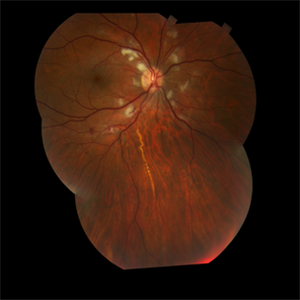

Bilateral Retinoschisis Retinal Detachment

Sep 15 2012 by Barbara Parolini, MD

Fundus photograph of a case of bilateral retinoschisis and retinal detachment. The border of the external layer breaks and the border of the schisis have been treated with argon laser. An epiretinal membrane formed after the formation of retinal detachment.

Photographer: Dr Rino Frisina, Istituto Clinico S.Anna, Brescia, Italy

Imaging device: optos

Condition/keywords: epiretinal membrane formation, retinoschisis